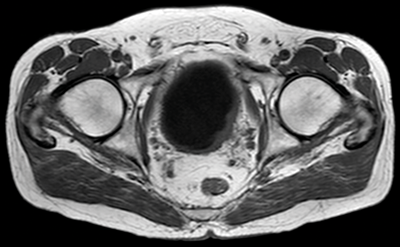

Figure 2. Axial T2 MRI showing a right sided tumour with the no evidence of extra-vesical extension.

T2 images should be obtained or reconstructed in three planes. T2 images allow assessment of the primary tumour and the bladder wall (Figure 2), and are superior to T1 images at assessing for invasion into adjacent organs such as the prostate or uterus. As well as axial imaging, a lateral bladder tumour or tumour at the dome is best assessed on coronal imaging, and an anterior tumour in the sagittal plane.